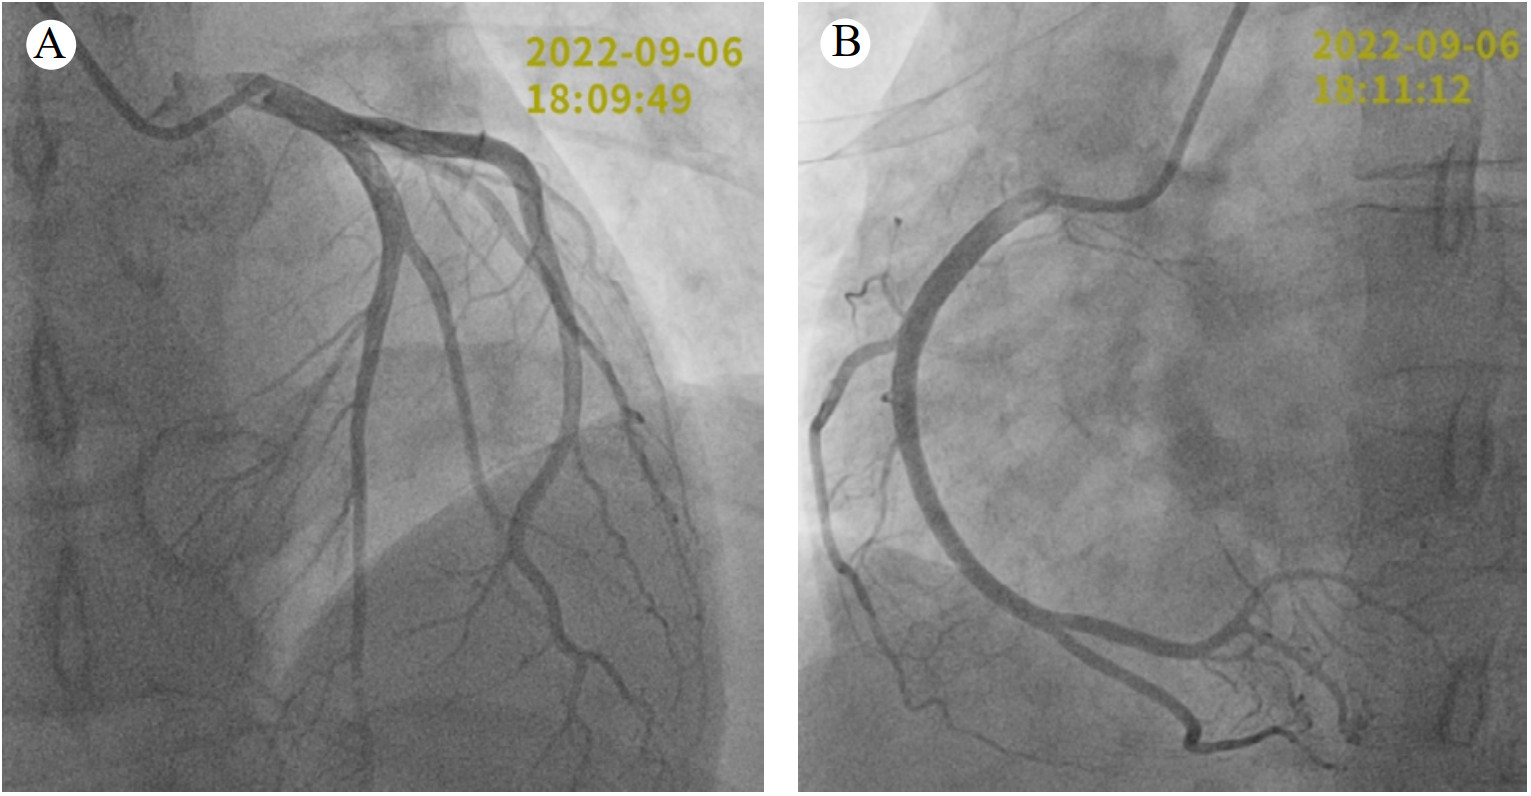

患者入内镜中心时心率74次/min,呼吸14次/min,血压115/70 mmHg(1 mmHg=0.133 kPa),氧饱和度99%,麻醉师给予瑞马唑仑10 mg、布托啡诺0.5 mg静脉注射诱导麻醉,昂丹司琼4 mg静脉注射预防呕吐,患者在麻醉用药后,未行胃肠镜前,立刻出现剧烈左侧胸痛,伴胸闷憋气,头痛、腹痛、恶心、大汗、无呕吐,无意识障碍,无肩背部疼痛,当时血压70/40 mmHg,立刻取消胃肠镜并行心电图示窦性心律,V2-V4导联ST段轻度压低(图 1)。给予补液治疗,患者胸痛持续20 min才较前缓解,但仍感胸闷,复测血压84/50 mmHg,遂行床旁超声心动图示左室射血分数56%,节段性室壁动度异常,室间隔中间段、左室下壁上1/2动度减低。随后由内镜中心转至急诊科,复查心电图示窦性心律,逆钟向转位,V2-V4导联ST段轻度压低消失(图 1),查心肌酶呈明显动态变化(表 1),查血常规:白细胞计数12.08×109/L,血红蛋白124 g/L,血小板计数231×109/L;肝肾功能、电解质、凝血功能、血气分析、超敏C反应蛋白、B型钠尿肽均正常,考虑不排除ACS,遂行冠脉造影检查,但术中未见冠脉异常(图 2),因此考虑SCM可能,术后转入心内监护病房观察,建议完善心脏磁共振,但患者拒绝,住院3 d自动出院。9月17日门诊复查超声心动图提示左室射血分数62%,仍有左室下壁上1/2动度略减低,但较11 d前室壁动度异常范围明显缩小,考虑SCM明确。2023年5月9日门诊再次复查超声心动图提示室壁动度正常。

| 注:A为左冠状动脉造影;B为右冠状动脉造影 图 2 9月6日患者冠状动脉造影结果 |